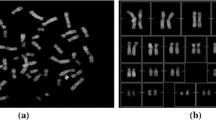

The genetic defects in the humans are uncovered by studying the chromosomes, as they are the genetic information carriers. They are non-rigid objects and they appear in different orientations when they are imaged. To find out the genetic defects, the chromosomes are pre-processed so that they are not touching, overlapping, and bent, and the noise is also discarded. The presence of bends, overlaps, or touches makes it difficult to uncover the genetic abnormalities. So there is a need for development of an efficient technique to classify the segmented chromosomes into different types and then pre-process them in order to correct their orientation. In this work, a hybrid classification technique based upon correlation-based feature selection and classification via regression approach, which will classify the segmented chromosomes into five categories viz; straight, overlapping, bent, touching, or noise is presented. The performance evaluation has been done using 1592 segmented chromosomes from Advance Digital Imaging Research data set. The over-all accuracy of 94.78 % has been obtained for the five class problem. The performance of the proposed classifier has been compared with Bayes Net, Naïve Bayes, Radial Bias Feed Forward Network, and k-nearest-neighbour classifiers. Based upon this categorization, different pre-processing techniques will be applied to correct the orientation of the chromosomes.